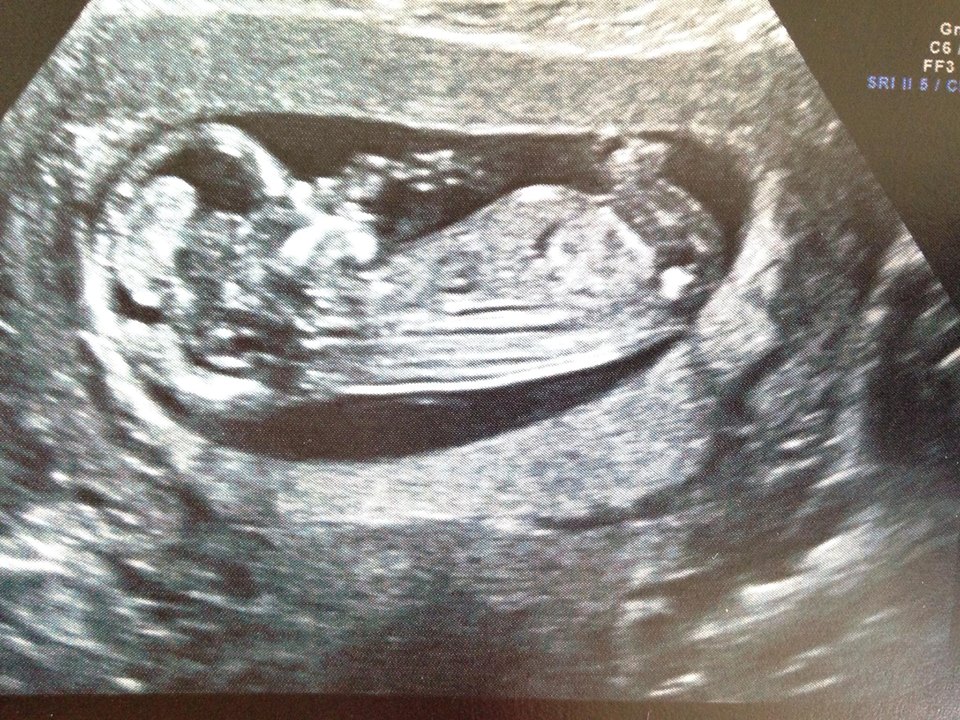

I had a 13 week scan last week, hoping to get a good nub shot. Unfortunately bub wasn't co-operating and wouldn't straighten out to get a shot. We did however get a 3D shot between the legs and the tech was confident it was a little boy.

I would love other opinions to see if you think she was right or if it's too early to tell.

I've included both photos.